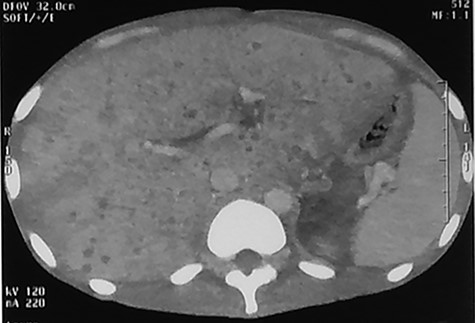

Abdominal CT scan at 3 months showed disappearance of the miliary abscess and also of the hepatomegaly (Fig. 2).

Abdominal CT scan (arterial phase) performed at 90th day after the beginning of the antibiotherapy showing normal liver parenchyma.